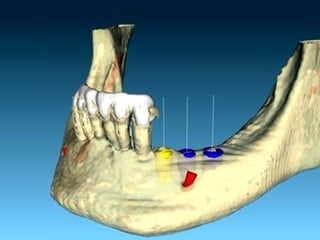

Diagnóstico en Implantología

• Clínico

• Por Imágenes Rx. Tomografía

• Modelos

Diagnóstico y Planificación

• Determina:

• - Si el paciente esta apto para la colocación de

implantes.

• - Tipo de prótesis.

• - Cantidad, distribución, diámetro, longitud,

posición y tipo de implante

Planificación

• Cantidad de implantes

• Distribución

• Alineación

• Nivel

• Paralelismo

• Tipo de prótesis